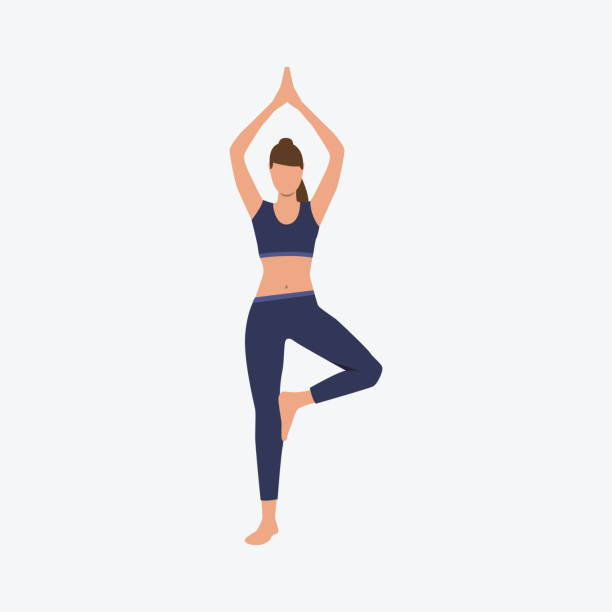

حرکت درخت

عالیترین ورزش برای صافشدن ستون فقرات و پیشگیری از شدت بروز اسکولیوز حرکت درخت است. جهت انجام این حرکت اصلاحی طبق روش زیر عمل کنید.

- پاهای خود را به اندازه عرض شانه باز کرده و در حالتی که مچ پا چپتان را خم کردهاید، وزن بدنتان را روی پای راستتان بیندازید.

- کف پای چپ خود را روی عضلات ران پای راست خود قرار دهید. کف دستها را روی هم گذاشته و آرنجها را خم کنید.

- تلاش کنید به مدت ۳۰ ثانیه در همین وضعیت باقی بمانید و تعادل بدنتان روی پای راست را کاملا حفظ کنید.